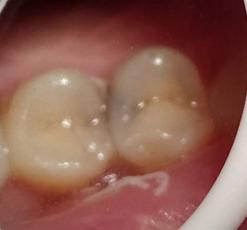

顾名思义,就是龋坏在相邻两颗牙齿之间,刚开始的时候从外面是基本看不出来的,可能只会出现吃东西时塞牙的症状。但如果通过专业检查配合拍X光片一般就能发现。

邻面龋主要是因为牙缝难以清洁,长期菌斑食物残留,牙齿邻接面被细菌侵蚀,慢慢缺损,因为位置比较隐蔽,不易发现,当发现的时候,缺损往往比较大了。